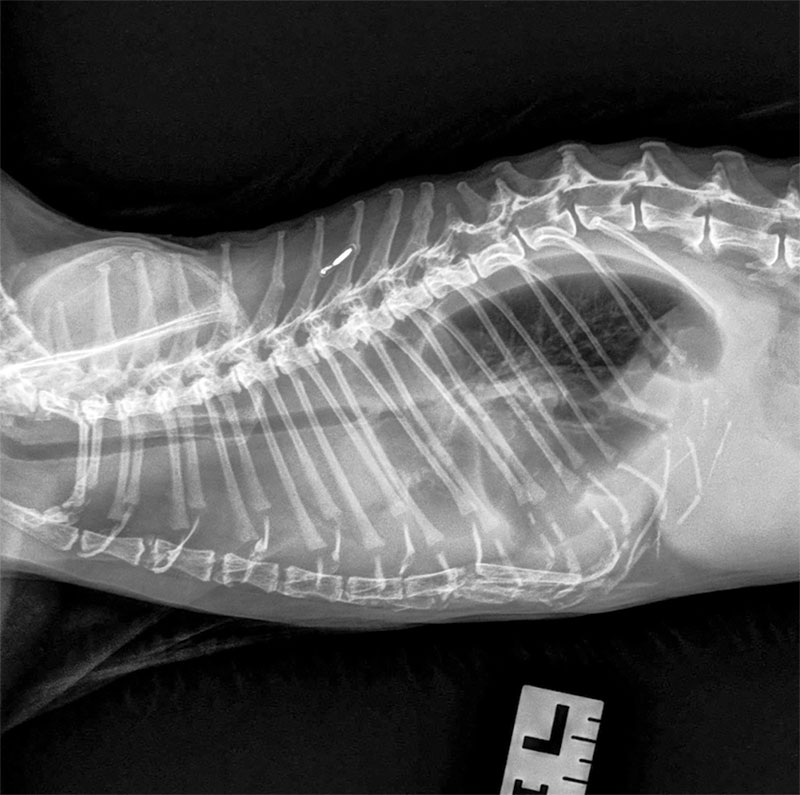

A 21-year-old cat presents for respiratory distress. Chylous effusion is removed via thoracocentesis.

A radiograph of a cat's lateral thorax.

Photo courtesy Dr. Kendra Freeman